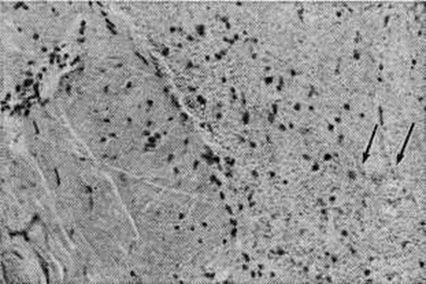

ПахименингитПахименингит (pachymeningitis; греческий pachys толстый, плотный + meninx, meningos оболочка + -itis) — воспаление твёрдой оболочки головного и спинного мозга. Воспалительный процесс твёрдой оболочки головного мозга называют церебральным пахименингитом, а твёрдой оболочки спинного мозга — спинальным пахименингитом. В зависимости от того, какие слои оболочки поражены, различают наружный, внутренний и внутри-оболочечный Пахименингит По характеру воспалительного процесса различают серозный, геморрагический и гнойный Пахименингит, по течению — острый и хронический Пахименингит Патологоанатомические изменения при серозном Пахименингит характеризуются разрыхлением, отёком и резким полнокровием твёрдой оболочки головного и спинного мозга. При геморрагическом внутреннем Пахименингит в патологический процесс вовлекается твёрдая оболочка головного мозга, чаще верхнелатеральной поверхности лобной и височной долей полушария головного мозга, иногда обоих полушарий мозжечка, реже области турецкого седла. В твёрдой оболочке спинного мозга геморрагический внутренний Пахименингит встречается крайне редко. При этой форме происходит геморрагическое пропитывание или расслоение твёрдой оболочки головного мозга вследствие разрыва стенок или флебита мозговых вен в зоне впадения их в синусы твёрдой мозговой оболочки. Макроскопически поражённая оболочка имеет пёстрый вид за счёт чередования буровато-коричневых старых очагов и скопления крови в образующихся в результате повторных кровоизлияний полостях (цветной рисунок 4). В дальнейшем содержимое полостей полностью обесцвечивается и образуются так называемый гигромы твёрдой оболочки головного мозга. Микроскопически при геморрагическом Пахименингит обнаруживаются очаги кровоизлияний разной давности и полости, внутренняя поверхность которых выстлана эндотелием (рисунок 1). Организация геморрагических масс (смотри полный свод знаний: Организация в патологии) происходит путём врастания в них грануляционной ткани с образованием тонкостенных сосудов (рисунок 2). В грануляционной ткани выявляются скопления гемолизированной крови и отложения гемосидерина; в формирующейся фиброзной капсуле отмечается пролиферация макрофагов (рисунок 3). Капсула может быть инфильтрирована лимфоидными и плазматическими клетками. Особенностью геморрагического Пахименингит является медленное развитие процессов организации и недостаточно выраженное свёртывание излившейся крови вследствие малого содержания в ней фибрина или примеси цереброспинальной жидкости. В центральных отделах полостей процессы организации могут развиваться быстрее, что сопровождается в ряде случаев отложением солей кальция или окостенением твёрдой оболочки головного мозга. При гнойном Пахименингит твёрдая оболочка головного и спинного мозга полнокровна, гнойный или фибринозно-гнойный экссудат располагается на наружной поверхности оболочки или в субдуральном пространстве, постепенно подвергаясь организации и отграничению спайками; при этом образуются экстра или субдуральные абсцессы. Микроскопически в твёрдой оболочке головного и спинного мозга обнаруживаются периваскулярные инфильтраты из сегментоядерных лейкоцитов и грануляционная ткань разной степени зрелости. При стихании процесса развивается фиброз оболочки. При хронический Пахименингит развивается фиброз твёрдой оболочки головного и спинного мозга и происходит сращение её с окружающими тканями. Распространение процесса по протяжению твёрдой оболочки спинного мозга способствует образованию муфтообразного утолщения с последующим сдавлением корешков спинномозговых нервов и их атрофией. При туберкулёзе, сифилисе, актиномикозе и других хронический инфекциях встречается хронический гиперпластический Пахименингит. Твёрдая оболочка спинного мозга при этом утолщена за счёт пропитывания желатинозным экссудатом, имеет желтовато-серый цвет, может быть сращена с окружающими тканями. Микроскопически обнаруживаются специфические гранулемы, при сифилисе преобладают гуммозные поражения. Церебральный пахименингит. Различают несколько форм церебрального Пахименингит: серозный церебральный Пахименингит, геморрагический внутренний и внутридуральный Пахименингит, наружный и внутренний гнойный церебральный Пахименингит |